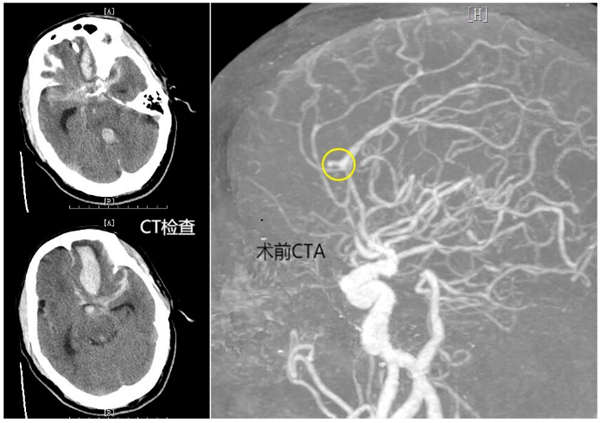

患者岑先生突發(fā)神志不清、呼之不應(yīng)。恩平市120急救中心快速將患者從當(dāng)?shù)匦l(wèi)生院轉(zhuǎn)至恩平市人民醫(yī)院開展進(jìn)一步救治,并提前開通生命綠色通道,完善初步CT檢查,并收入ICU。根據(jù)患者病程及CT結(jié)果,恩平市人民醫(yī)院神經(jīng)外科診斷為顱內(nèi)動(dòng)脈瘤破裂出血。

時(shí)間就是生命,恩平市人民醫(yī)院立即啟動(dòng)多學(xué)科聯(lián)合診療應(yīng)急處置預(yù)案,一方面由ICU快速行氣管插管、呼吸機(jī)輔助呼吸、降顱壓等治療。同時(shí),聯(lián)合放射科、醫(yī)學(xué)檢驗(yàn)科、麻醉手術(shù)科、導(dǎo)管室等科室開放快速診療通道。急查頭頸部CTA提示:左側(cè)大腦前動(dòng)脈瘤、左額葉大量腦出血破入腦室、蛛網(wǎng)膜下腔出血。